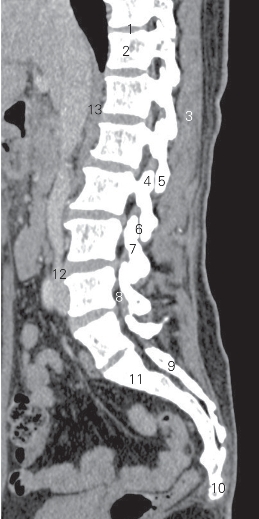

图3-6 经脊柱的旁正中矢状断层CT图像(软组织窗)

1 第10胸椎间盘 10th thoracic intervertebral disc

2 第11胸椎椎体 11th thoracic vertebral body

3 竖脊肌 erector spinae 4 上关节突 superior articular process

5 下关节突 inferior articular process 6 关节突关节 zygapophysial joints

7 关节突间部 intermediate part of articular process

8 椎间孔 intervertebral foramen 9 骶中间嵴 intermediate sacral crest

10 尾骨 coccyx

11 第1骶椎椎体 1st sacral vertebral body

12 下腔静脉 inferior vena cava 13 右膈脚 right crus of diaphragm